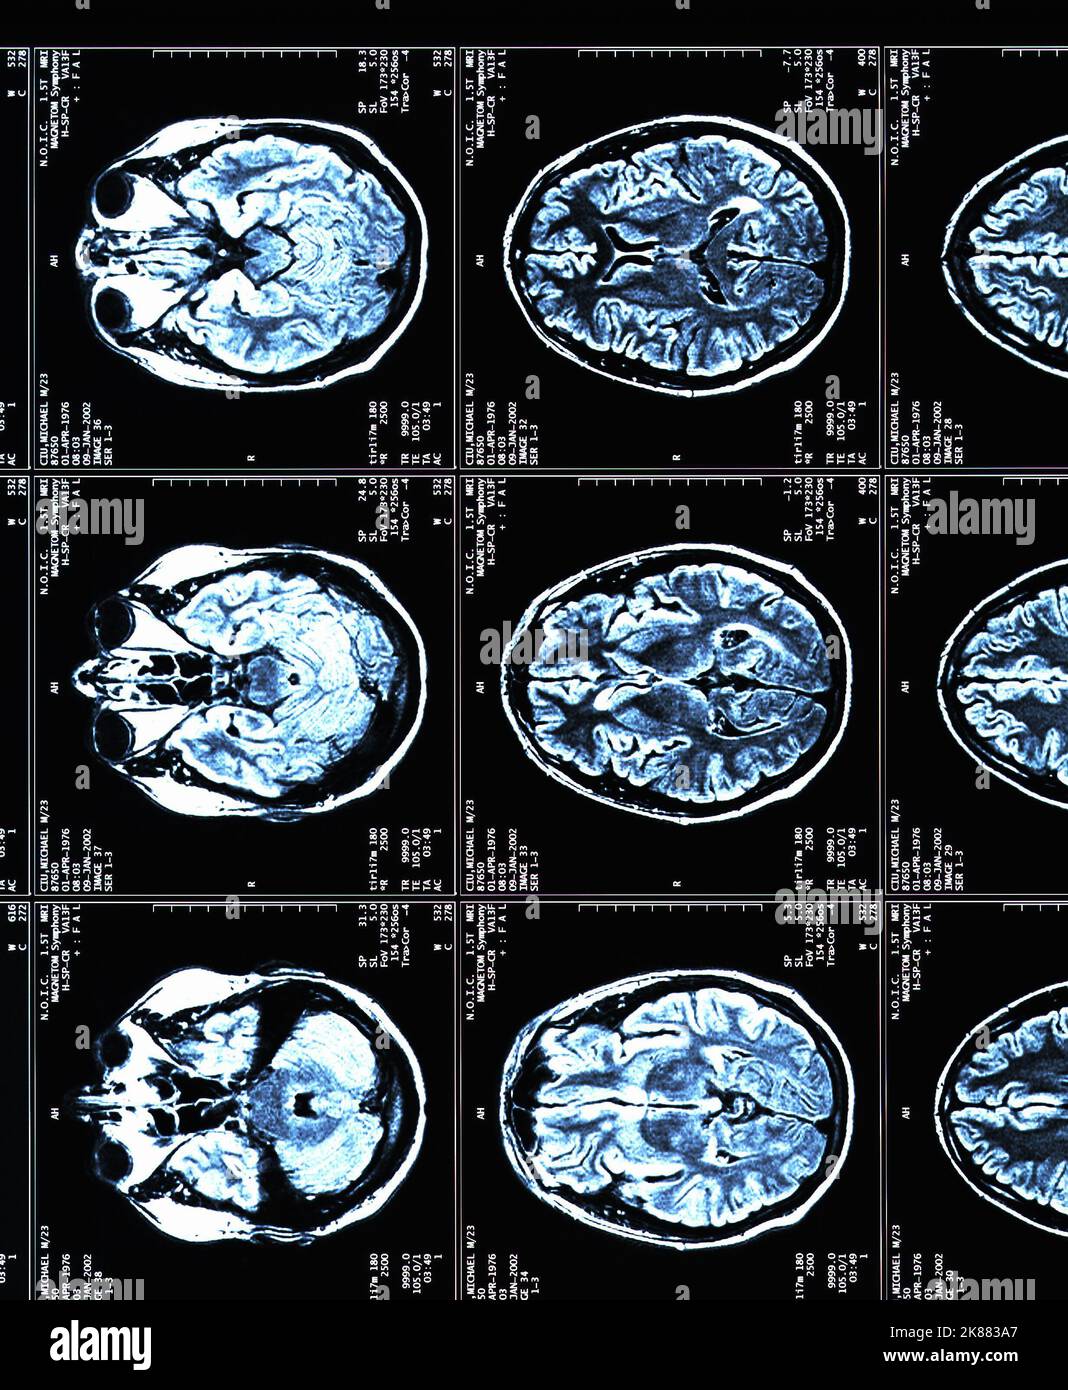

from radiologycases.my

Multiple Sclerosis Radiology Cases